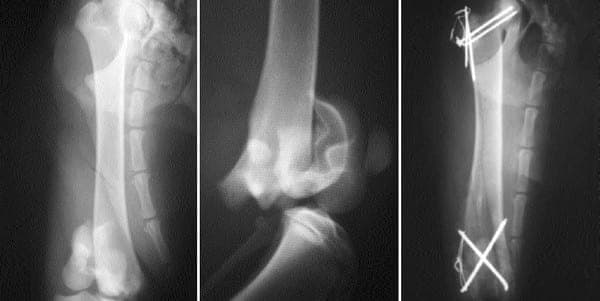

Se cayó desde unos tres metros de altura y presentaba una fractura supracondilar (figura 2). Como tratamiento quirúrgico se eligieron dos agujas cruzadas en forma de aspa de 1,5 mm y una tercera aguja de 1 mm auxiliando la estabilidad final.

Figura 2. Fractura supracondilar de fémur. Figura 3. Radiografía postoperatoria. Se ha conseguido una correcta reducción.

La evolución fue excelente, con una recuperación tanto funcional como radiológica de la extremidad muy rápida (figura 3). En un control radiográfico realizado a las 5 semanas de la intervención se apreciaba una consolidación muy estable sin que se pudiese ver ya la línea de la fractura.